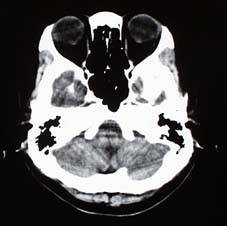

腹 部 頭 部 頭 部

頭部3DCTA(CT血管造影)